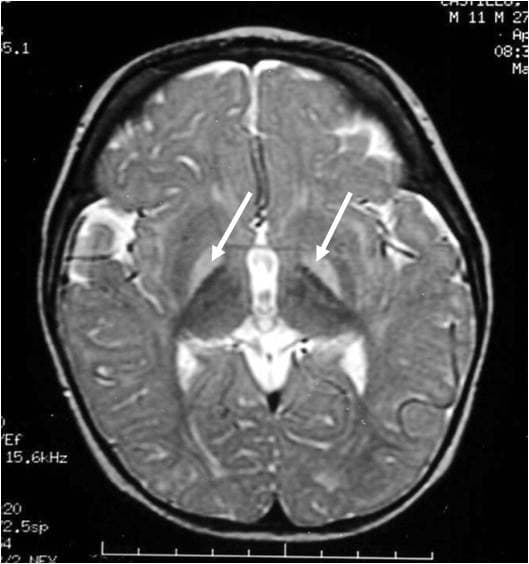

L'ictère nucléaire désigne le stade avancé de l'atteinte cérébrale chez le nouveau-né secondaire à l'accumulation de bilirubine (ictère). La bilirubine libre, c'est-à-dire non conjuguée, si elle est trop élevée (au-delà de 250 à 300 μmol/L (environ 14,5 à 17,5 mg/dL) chez l'enfant à terme) se fixe sur les noyaux gris centraux entraînant des lésions cérébrales et une atteinte des nerfs crâniens (le en particulier) irréversibles à ce stade. Cette augmentation de la bilirubine est liée à une hyper-hémolyse d'une part, et/ou au retard (prématurité) ou à l'absence de la mise en route des enzymes hépatiques nécessaires à la glycuroconjugaison de la bilirubine. Cette glycuroconjugaison était inutile in utero, la bilirubine étant éliminée par voie placentaire. In vitro, la bilirubine libre altère le nombre de dendrites, d'axones et des synapses des neurones et joue sur les cellules gliales. Au niveau biochimique, cette molécule stimulerait le stress oxydatif, favorisant l'oxydation des protéines et la peroxydation des lipides, inhibant les défenses anti-oxydatives de la cellule. Cette hyperbilirubinémie est souvent due à une incompatibilité fœto-maternelle entrainant une hyperhémolyse. D'autres affections peuvent causer cet ictère nucléaire, entre autres : Maladie de Crigler Najjar, par absence de glycuroconjugaison par déficit en UGT1A1. ou par anomalie érythrocytaire entrainant une hyperhémolyse : Déficit en G6PD, Maladie de Minkowski-Chauffard La prématurité, le poids faible de l'enfant majorent le risque d'atteinte pour des taux plus faibles de bilirubine. Outre l'ictère, ce sont les symptômes neurologiques qui sont au premier plan, avec un risque de séquelles : syndrome extrapyramidal, mouvements de type chorée-athétose, parésie oculomotrice et surdité. Son incidence est inférieure à 3 cas pour 100 000 naissances, mais elle peut être beaucoup plus fréquente dans les pays en voie de développement. L'ictère nucléaire tend à réapparaitre, et pas seulement en France, dans la mesure où l'enfant n'est pas surveillé pendant sa première semaine de vie du fait des sorties de plus en plus précoces de la maternité.